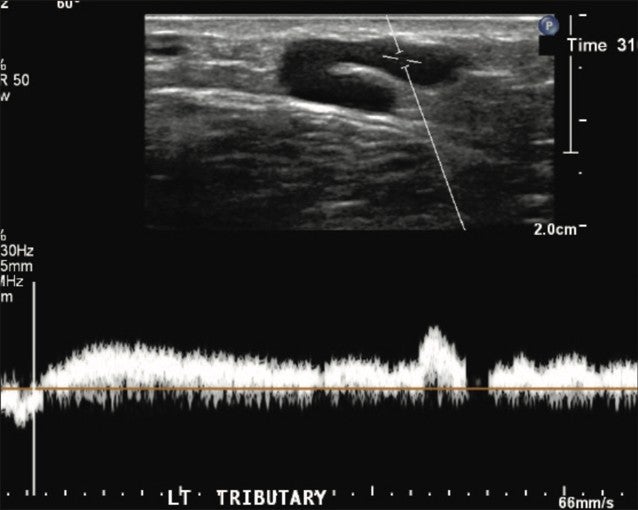

A GSV reflux pattern was observed at the thigh level and extended distally. Vein diameters ranged from 4.7-5 .1mm in the largest associated GSV tributary vein. Reflux times ranged from 2-3.2 seconds.

Figure 2. Left GSV tributary vein showing an abnormal, refluxing Doppler signal.